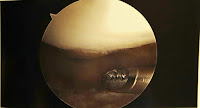

| See the problem here? Cool photos from inside my right knee. |

| All clean! Except you can see the little half-moon shadow where there should be cartilage, and there just isn’t. |